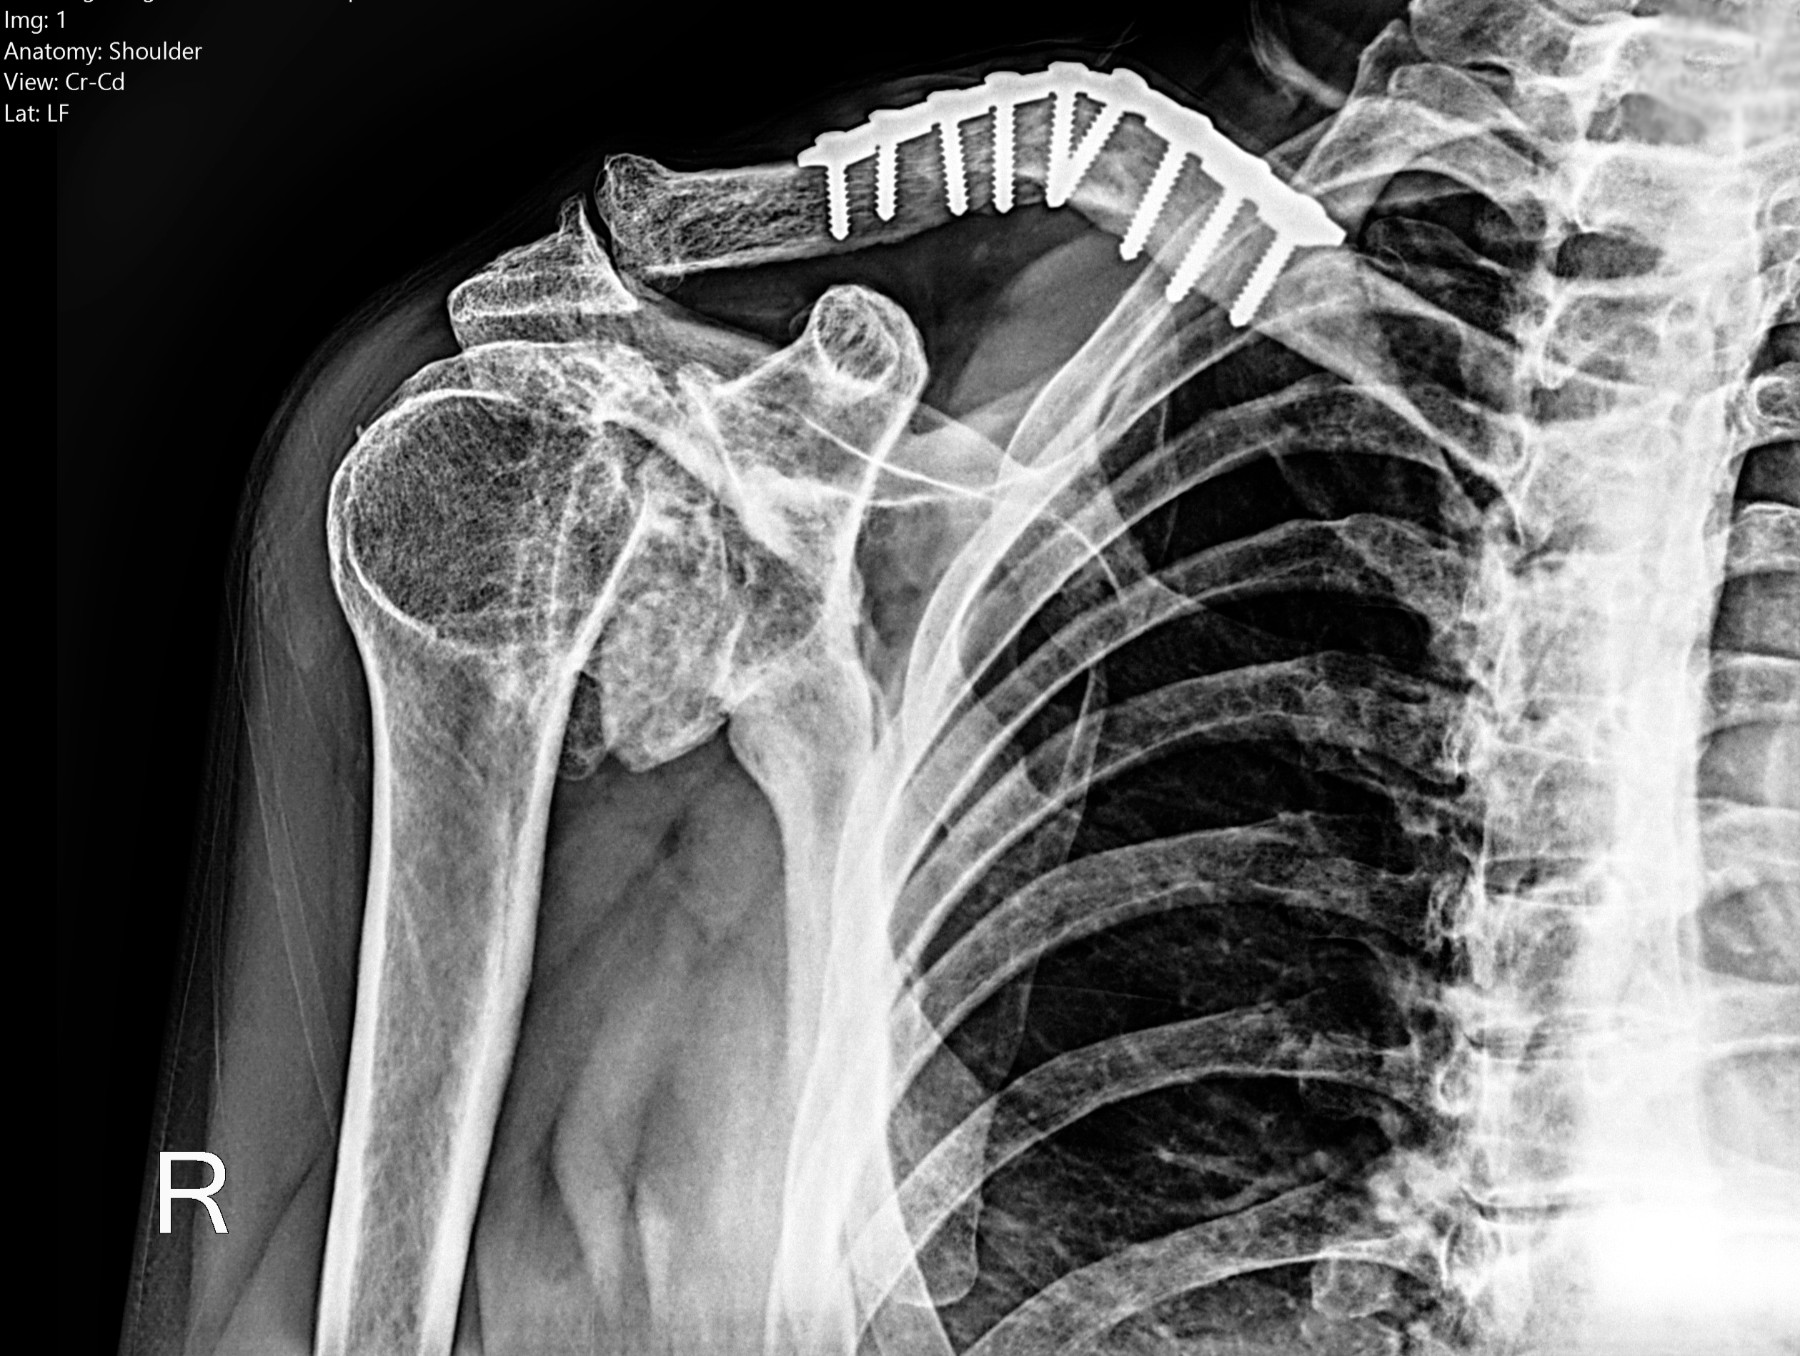

Cambios Térmicos en las Extremidades de Caballos,

Asociados a Golpes y su Evaluación por Termografía.

Los caballos de salto, en competencia, pueden derribar obstáculos y lastimarse. Si se golpean, no siempre claudican. Considerando al calor como un signo de inflamación, se evaluaron los cambios térmicos de 6 áreas de las extremidades torácicas y pelvianas de 23 caballos de salto en nivel de competencia de 1.05 a 1.60 m de altura, por medio de termografía durante 4 días de competencia (N=2208 áreas).